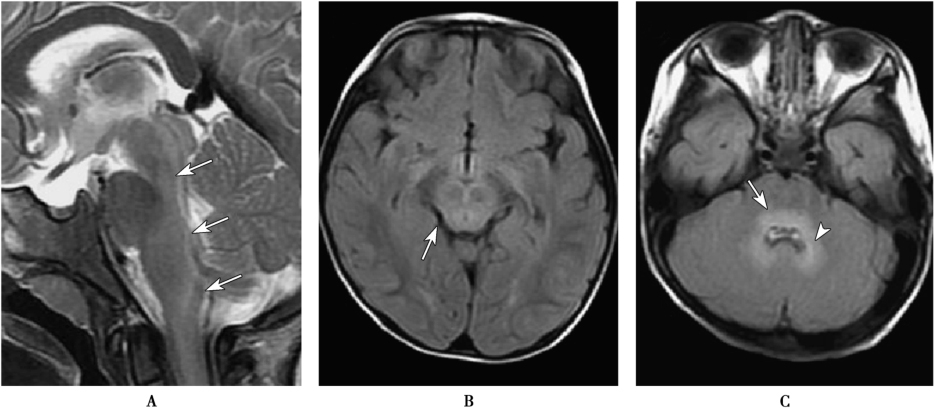

颅脑CT检查可用于鉴别颅内出血、脑疝、颅内占位等病变。神经系统受累者MRI检查可出现异常改变,合并脑干脑炎者可表现为脑桥、延髓及中脑的斑点状或斑片状长T1长T2信号(图2)。并发急性弛缓性麻痹者可显示受累节段脊髓前角区的斑点状对称或不对称的长T1长T2信号。

图2脑干脑炎

A.矢状面T2WI显示大脑脚至颈髓的脑干背侧有连续的斑片状高信号(白色箭头);B.FLAIR显示中脑呈高信号(白色箭头);C.FLAIR,在脑桥背部(白箭)和齿状核(白色箭头)显示高信号